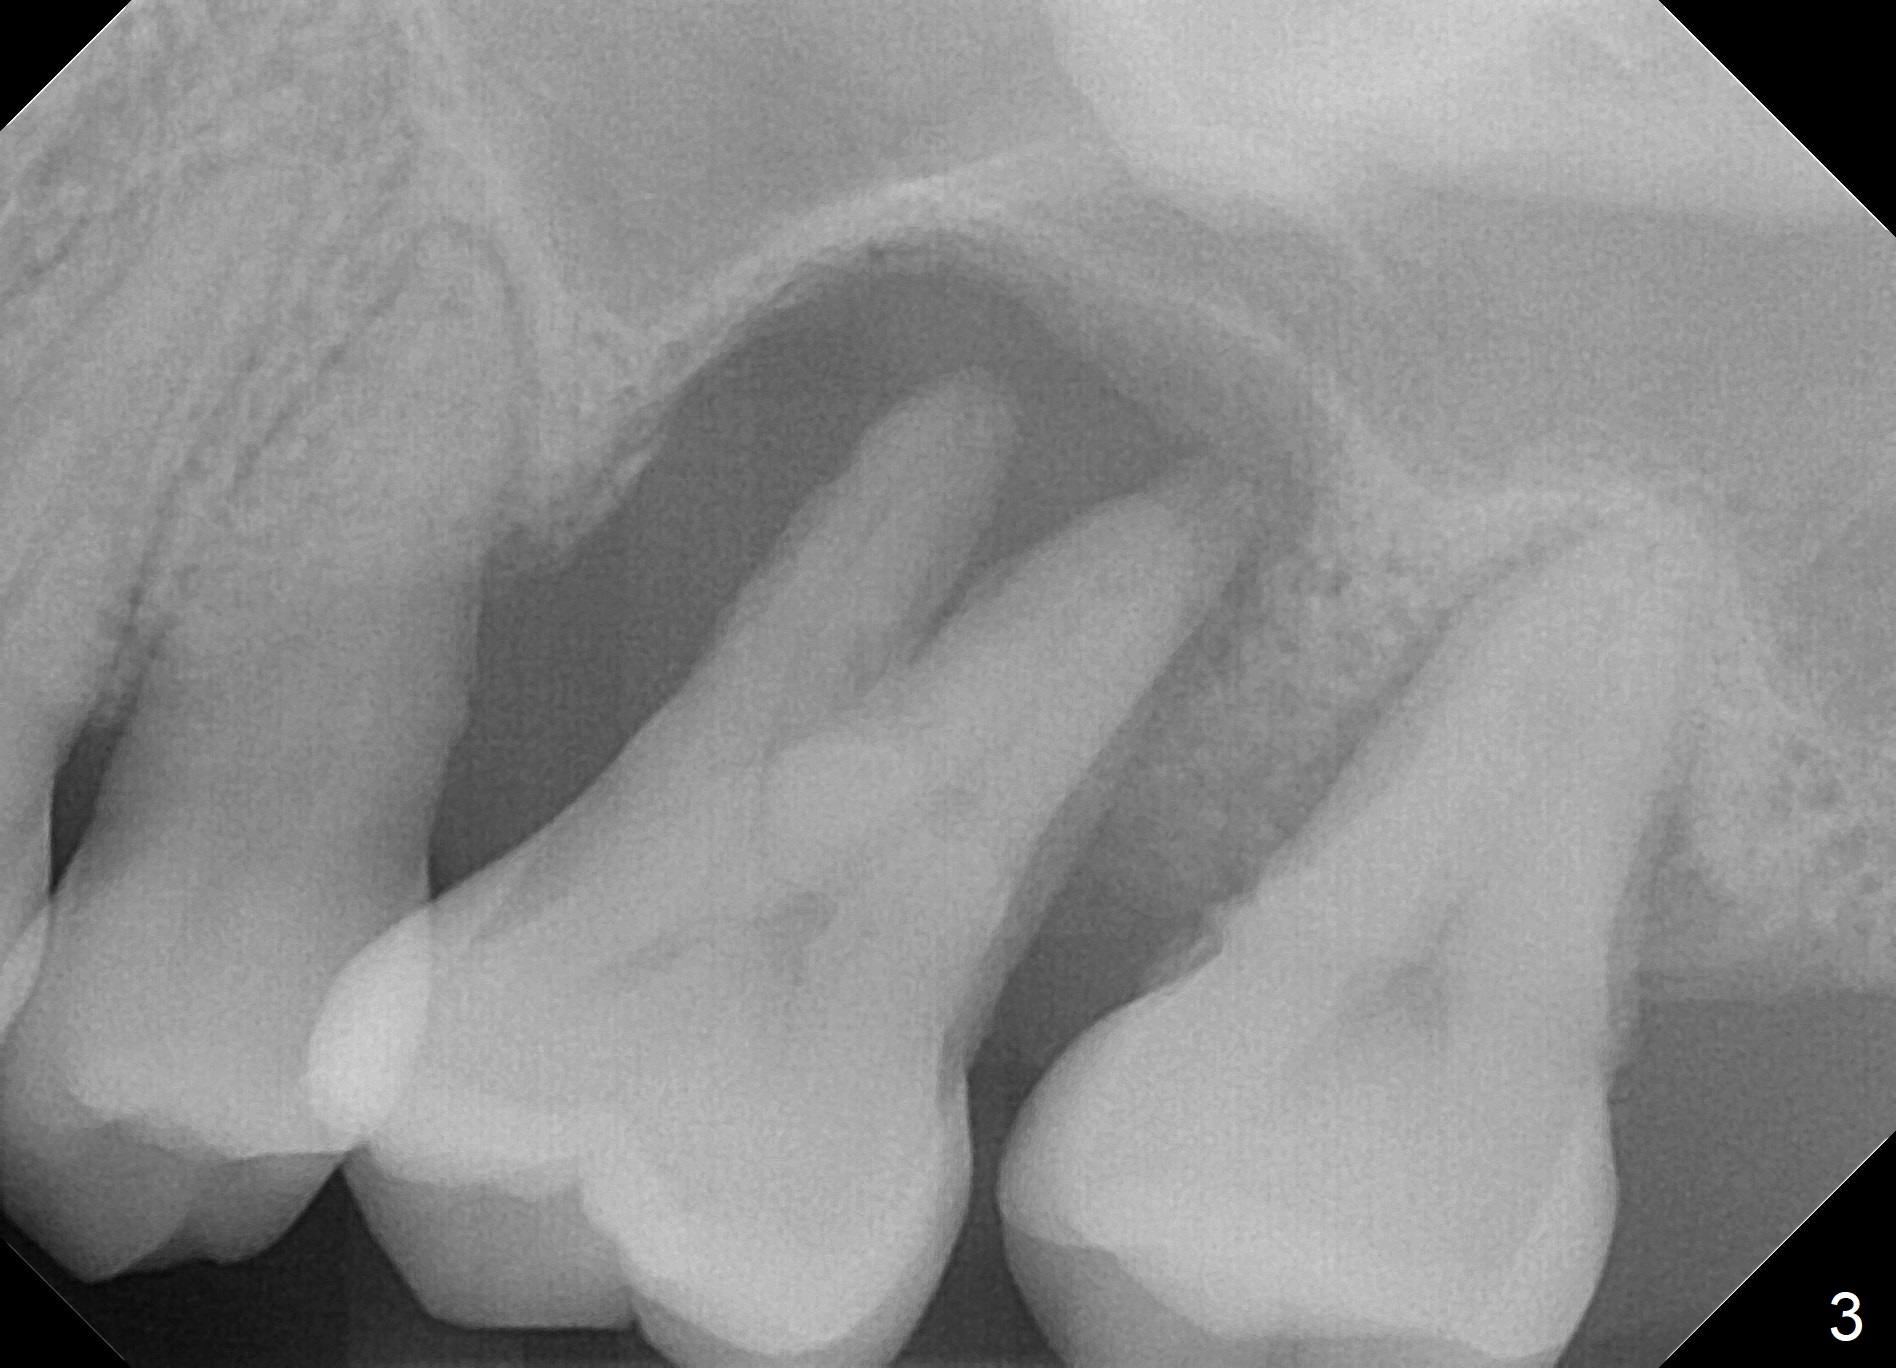

A 41-year-old man has had severe periodontitis at #14 for the last 11 years (Fig.1-3). Finally the tooth is mobile. Draw blood for PRF membrane (x4). After use of Magic Drill with 3 mm stopper, tap Magic Lifter for sinus lift. Insert 1-2 PRF membrane(s) and Vanilla graft prior to further osteotomy with UF drills until 4.5 or 5 mm. Insert tap drill for primary stability. If it fails, switch to IBS dummy implants.